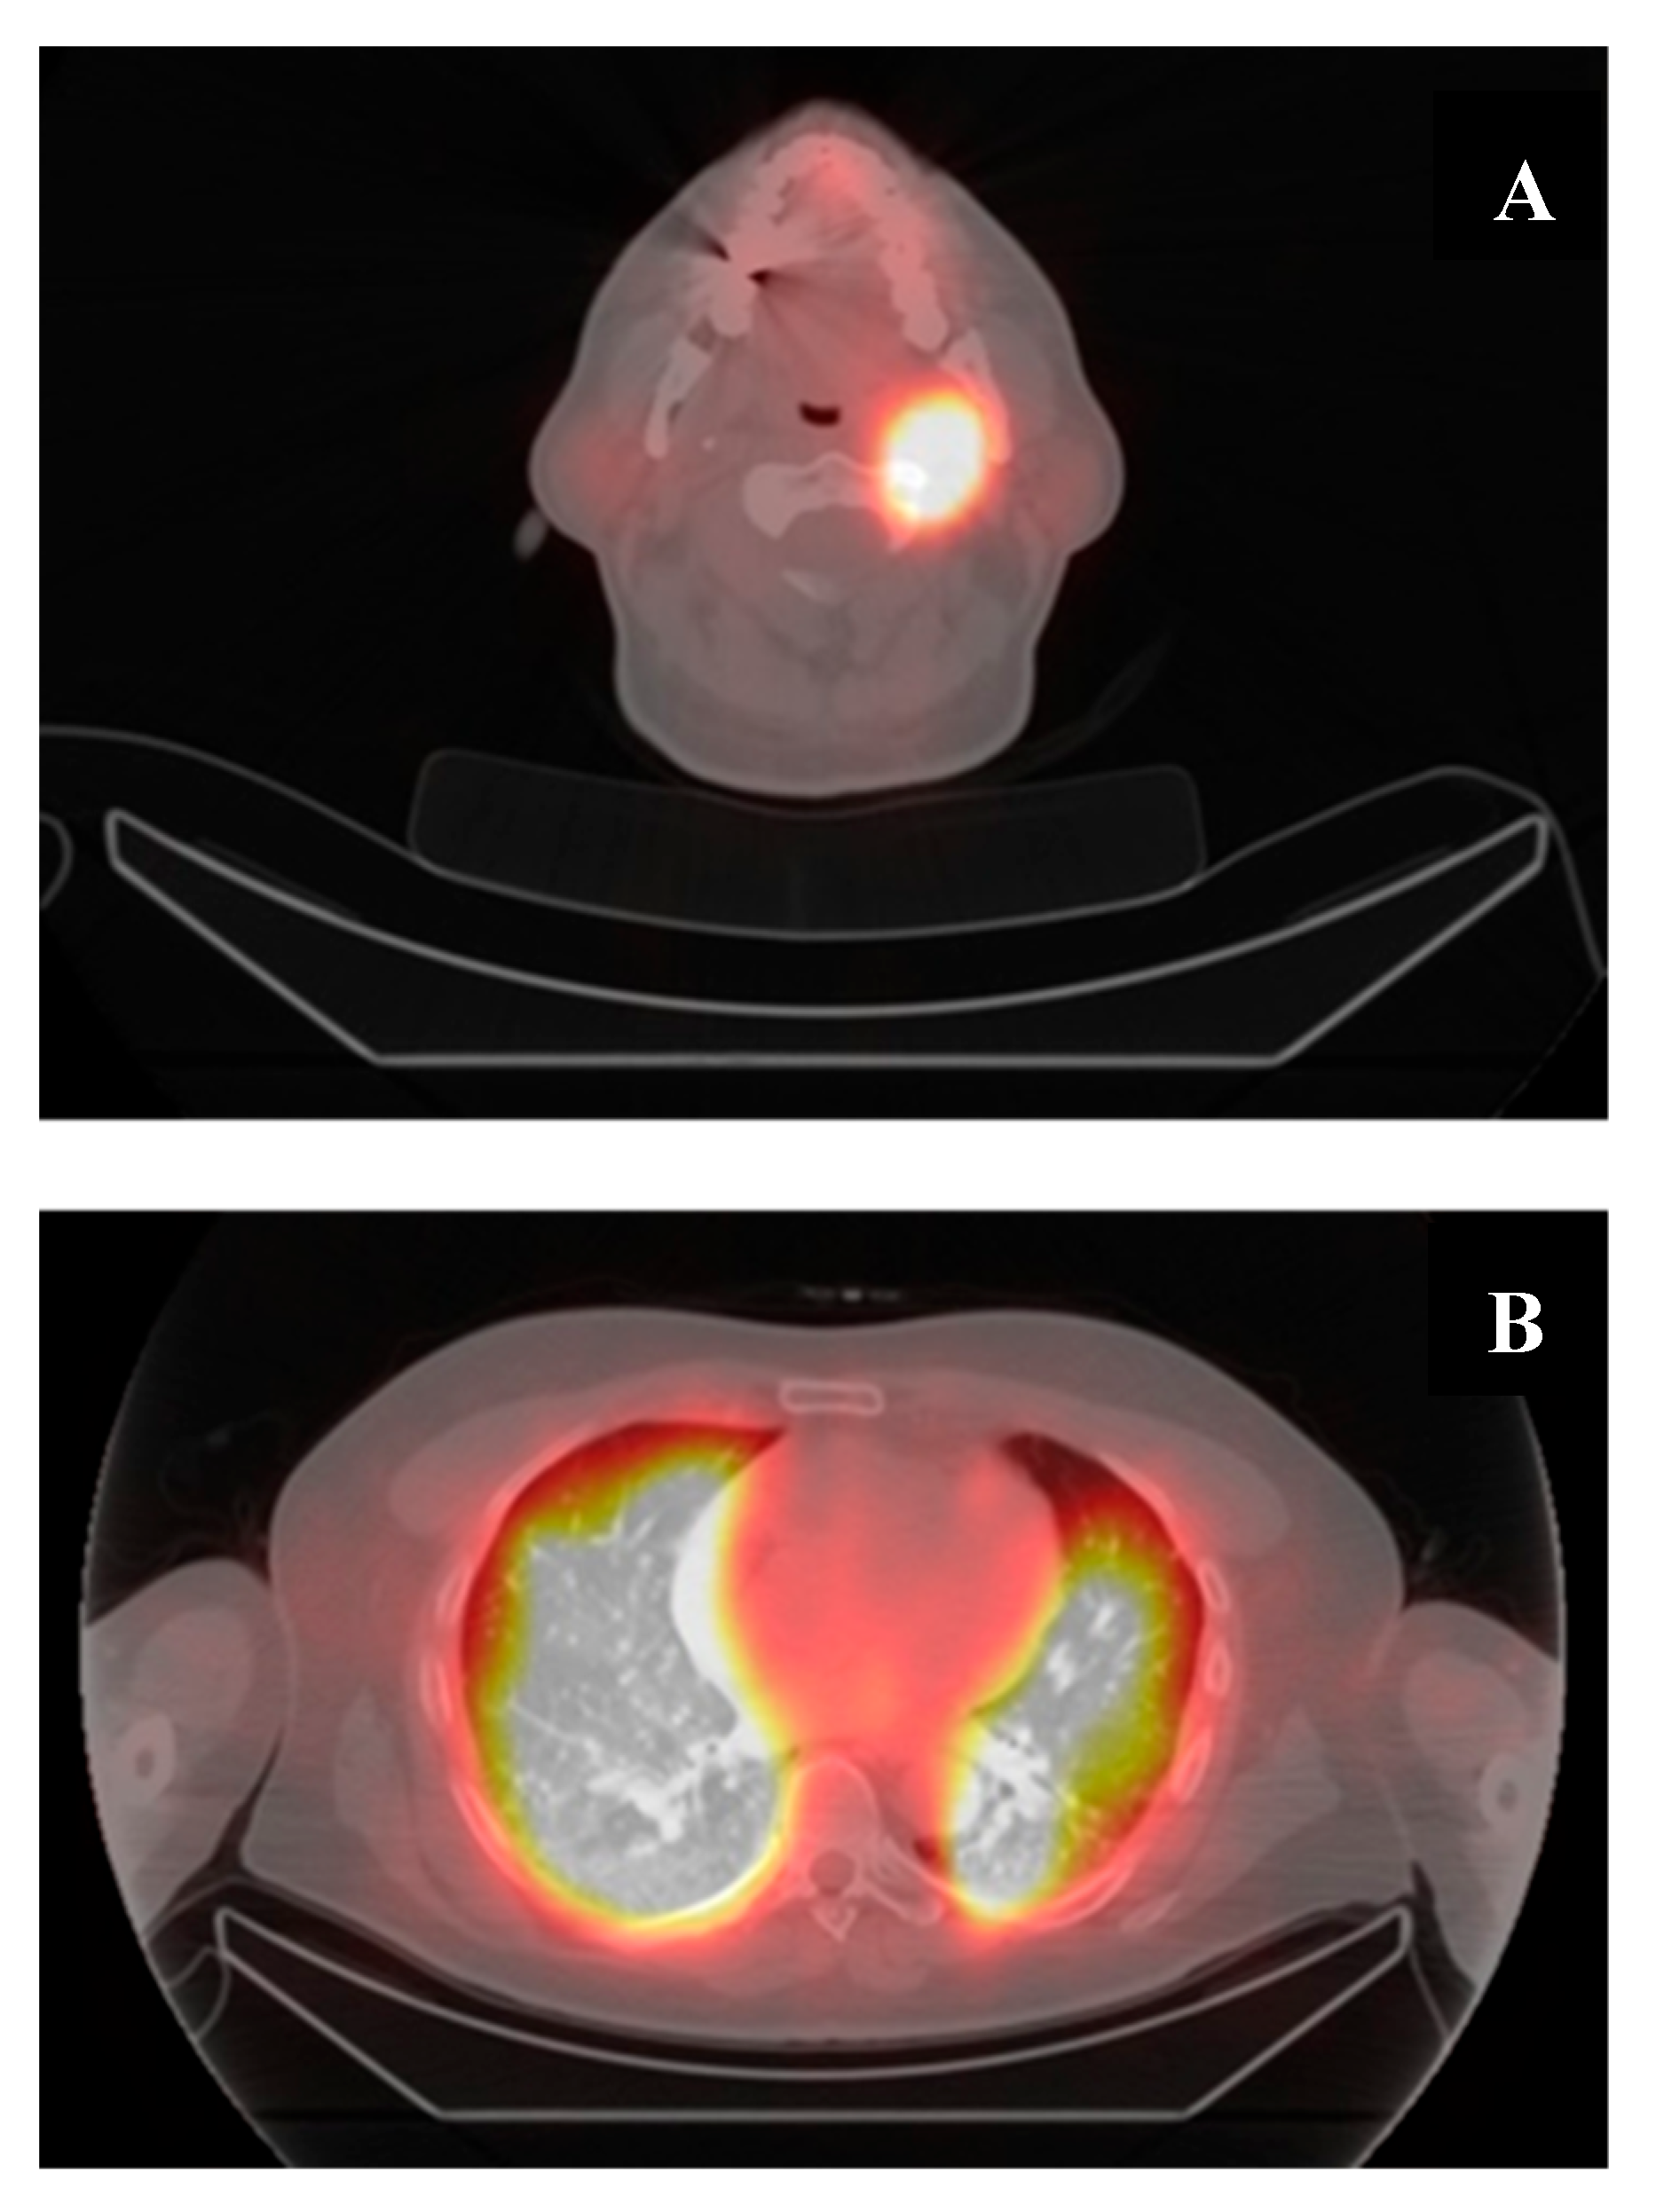

6. A Case of Re-Differentiation